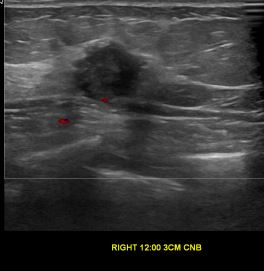

상기환자는 우측 유방통증과 멍우리있어 내원하신 70대초반 여성분으로 의심스러운 우측혹 조직검사 시행해 침윤성유방암으로 진단되었습니다